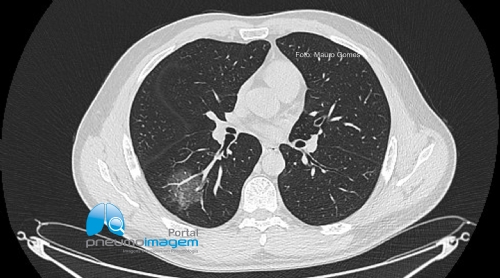

CASO CLÍNICO #60

Homem de 48 anos, diabético controlado, compareceu ao PS com história de febre e mialgia, sem outros sintomas. Qual o seu provável diagnóstico e conduta? Deixe seus comentários abaixo.

A 48-year-old man, a controlled diabetic, attended the ER with a history of fever and myalgia, without other symptoms. What is your probable diagnosis and conduct? Write your comments below.